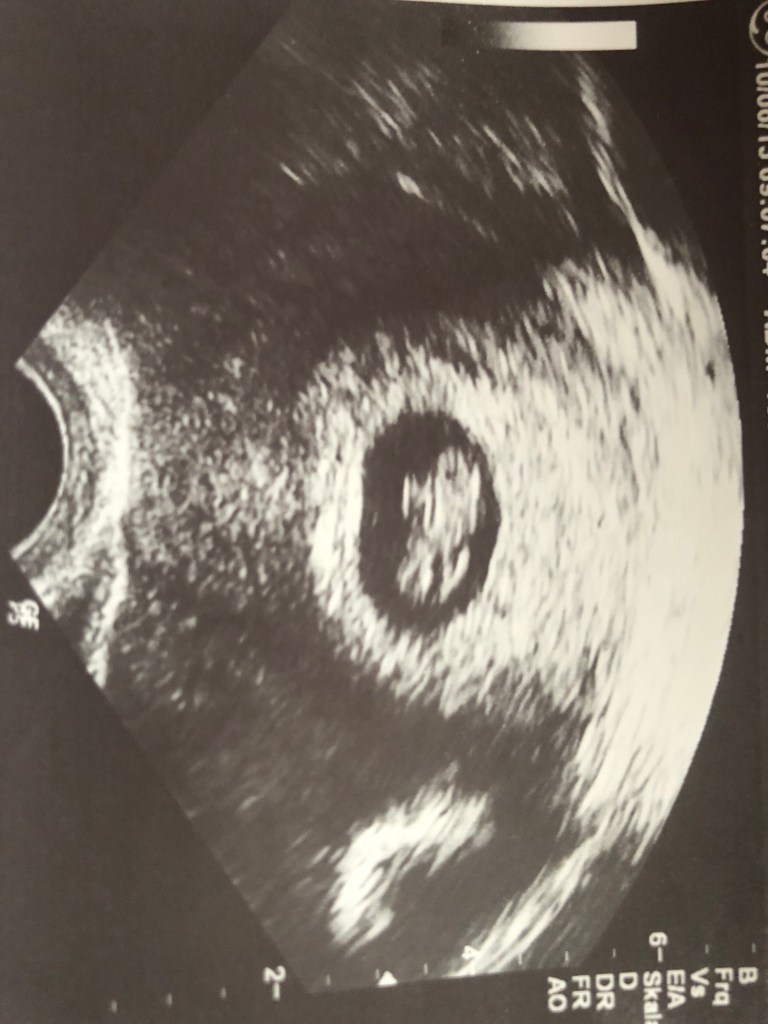

Die Nacht war schlecht, ich habe kaum ein Auge zu gemacht, denn heute war der Tag, heute mache ich einen Schwangerschaftstest. Ganz früh am Morgen schlich ich mich aus dem Bett und ließ meine Bande noch ein bisschen schlafen, denn es war ja schließlich Sonntag.😊Ich fühlte mich schon seit 2-3 Tagen recht unwohl, beklagte mich bei meiner lieben Arbeitskollegin, dass mir die Brüste weh tun und sie schaute mich schon schmunzelnd an. Die 5 Minuten, bis das Ergebnis angezeigt wurde, kamen mir wie eine Ewigkeit vor… doch dann stand es klar und deutlich da: „schwanger“, ich war wie in Trance, wusste meine Gefühle in diesem Moment nicht einzuordnen. Mir liefen die Tränen über das Gesicht, wie sehr haben wir uns ein Geschwisterchen für unsere Leni gewünscht. Ich stürmte aus dem Bad, Tobias stand im Wohnzimmer, ich rannte auf ihn zu und fiel ihm weinend in die Arme. Viel musste ich nicht sagen, er verstand sofort und nahm mich fest in seine Arme. Dieses Gefühl, unbeschreiblich. Leni ließen wir vorerst nichts davon wissen, denn vor dem Besuch beim Arzt, der die Schwangerschaft bestätigt, wollte ich sie nicht aufwühlen. Montag rief ich bei meinem Arzt an und machte daraufhin einen Termin für 1 Woche später. Und ja, er bestätigte tatsächlich dieses kleine Wunder in meinem Bauch. Seine Worte zum Abschied waren: „Passen sie gut auf sich auf.“ Natürlich passe ich auf mich auf, warum betont er das denn jetzt so? Die Schwangerschaft mit unsere Leni war doch wie im Bilderbuch.. doch dieses Mal sollte es etwas anders werden ..